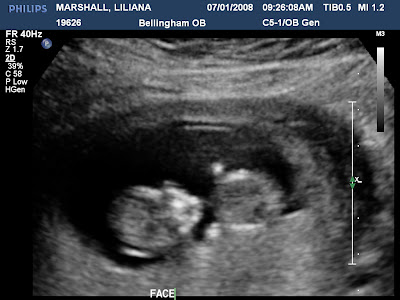

We are so excited because we have about 4 1/2 weeks until our big ultrasound!!! We'll know the sex (if baby cooperates) on August 22

nd!!! I can't wait to know whether it's Magdalen Grace or Benjamin

Dariel!!! No more calling baby 'it'. Yeah!!